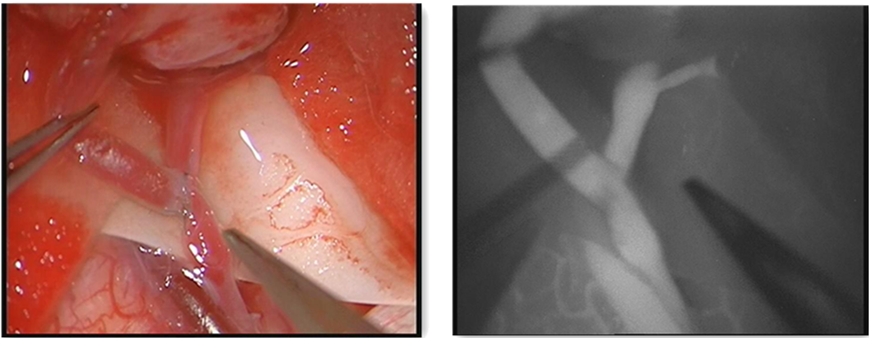

术中显微镜下证实桥血管通畅 术中荧光造影显示桥血管通畅